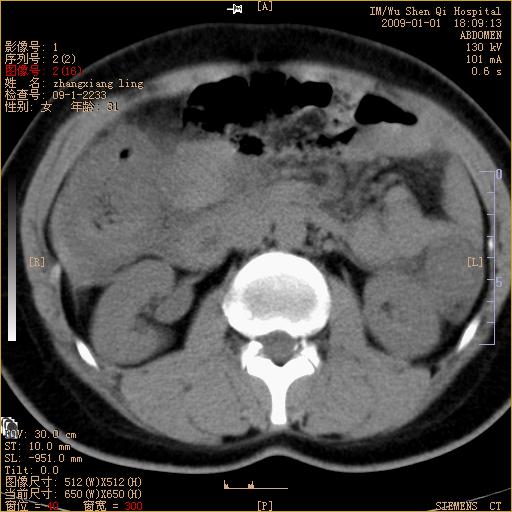

标题: CT17527:F31Y,腹痛伴血便9小时 [打印本页]

标题: CT17527:F31Y,腹痛伴血便9小时

升结肠肠壁不规则增厚,肠腔狭窄,考虑升结肠占位,建议增强扫描

升结肠肠壁不规则增厚,肠腔狭窄,考虑升结肠占位,建议增强扫描,不除外肠套叠.

升结肠肠壁不规则增厚,似呈同心圆改变,其有积液。结合病史首先考虑肠套叠伴肠壁坏死可能性大,结肠肿瘤待排。

患者已手术,结果肠系膜血栓形成肠坏死

结果:患者已手术,结果肠系膜血栓形成肠坏死。回过头再看局部肠壁增厚有分层(高密度坏死及低密度水肿)表现。